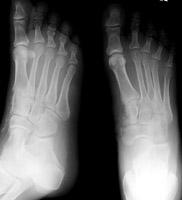

AP and oblique radiographs of the foot. A car ran over the foor of this patient. There is a comminuted fracture of the medial cuneiform bone along with fractures of the navicular and first metatarsal.